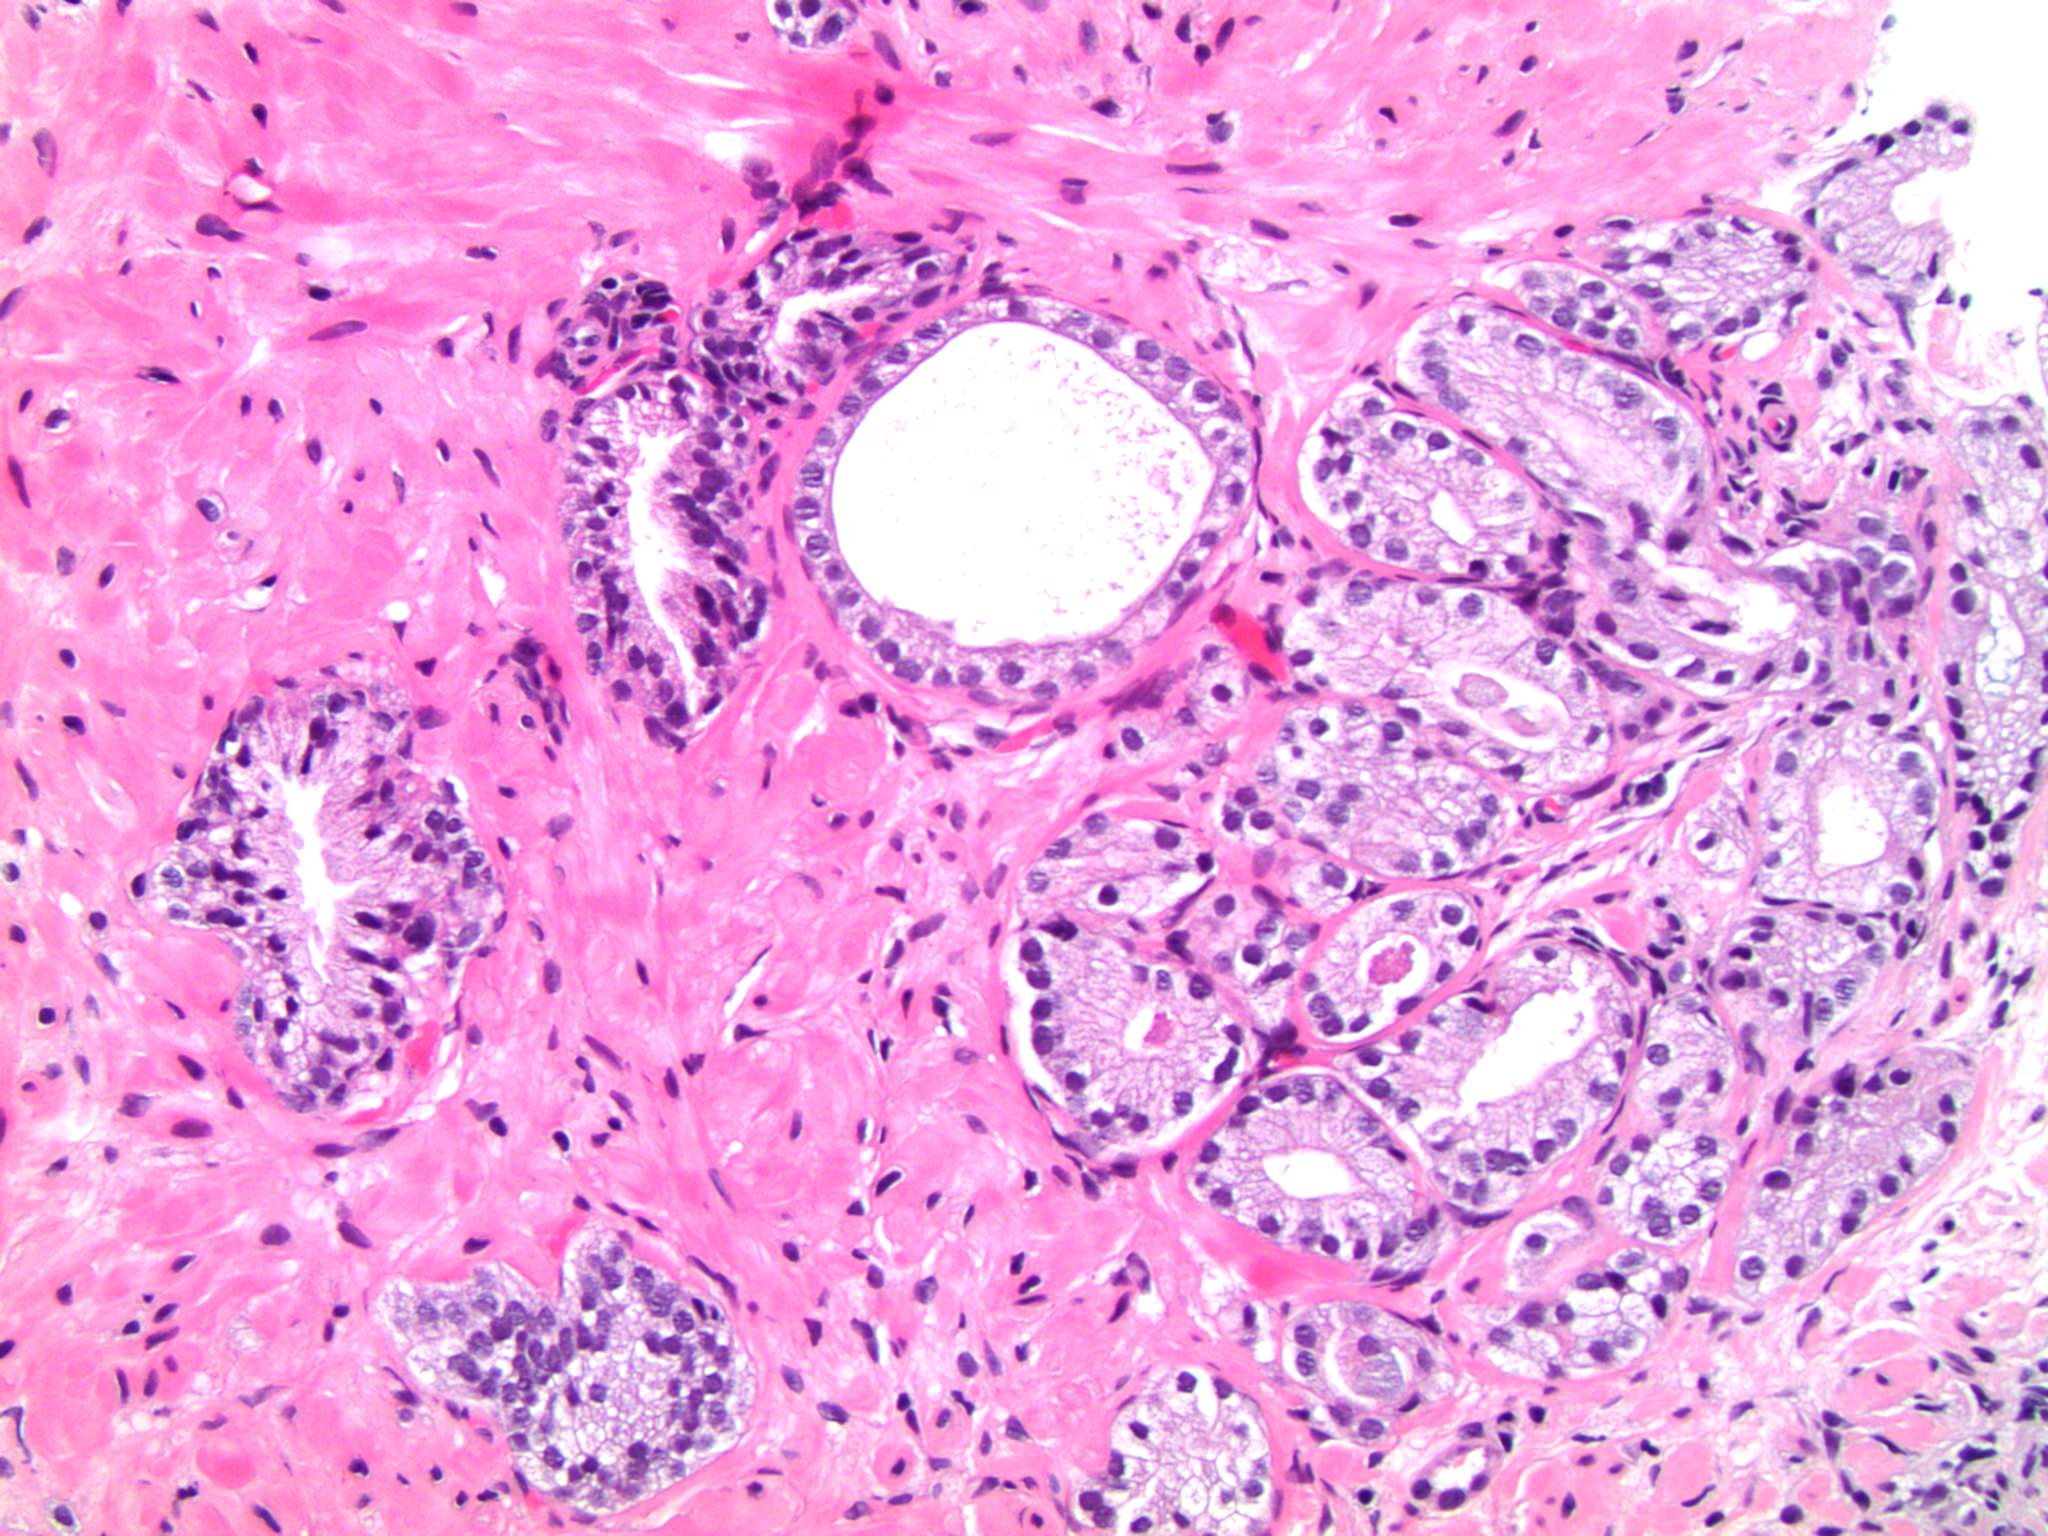

An update on atypical large glandular proliferations of the prostate What Is Atypical Glandular Proliferation Atypical cells don't necessarily mean you have cancer. Atypical glandular cells (agc) this article will focus on the most serious of these categories: The abnormal cells may have come from the tissue lining the inside of the endometrium or the cervix. Learn what atypical, atypical small acinar proliferation or atypical glandular proliferation findings mean in your prostate pathology report. When. What Is Atypical Glandular Proliferation.

An update on atypical large glandular proliferations of the prostate What Is Atypical Glandular Proliferation Atypical glandular cells (agc) is a term used to describe abnormal cells found in a cervical pap test. Atypical cells don't necessarily mean you have cancer. Atypical glandular cells (agc) this article will focus on the most serious of these categories: When viewed with a microscope, the cells look different from typical breast cells. However, it's still important to make. What Is Atypical Glandular Proliferation.

An update on atypical large glandular proliferations of the prostate What Is Atypical Glandular Proliferation Atypical glandular cells (agc) is a term used to describe abnormal cells found in a cervical pap test. Atypical hyperplasia causes a buildup of cells in the breast tissue. Atypical cells don't necessarily mean you have cancer. Atypical glandular cells (agc) are rare abnormalities found on cervical cytology associated with a range of lesions of the female reproductive. The abnormal. What Is Atypical Glandular Proliferation.